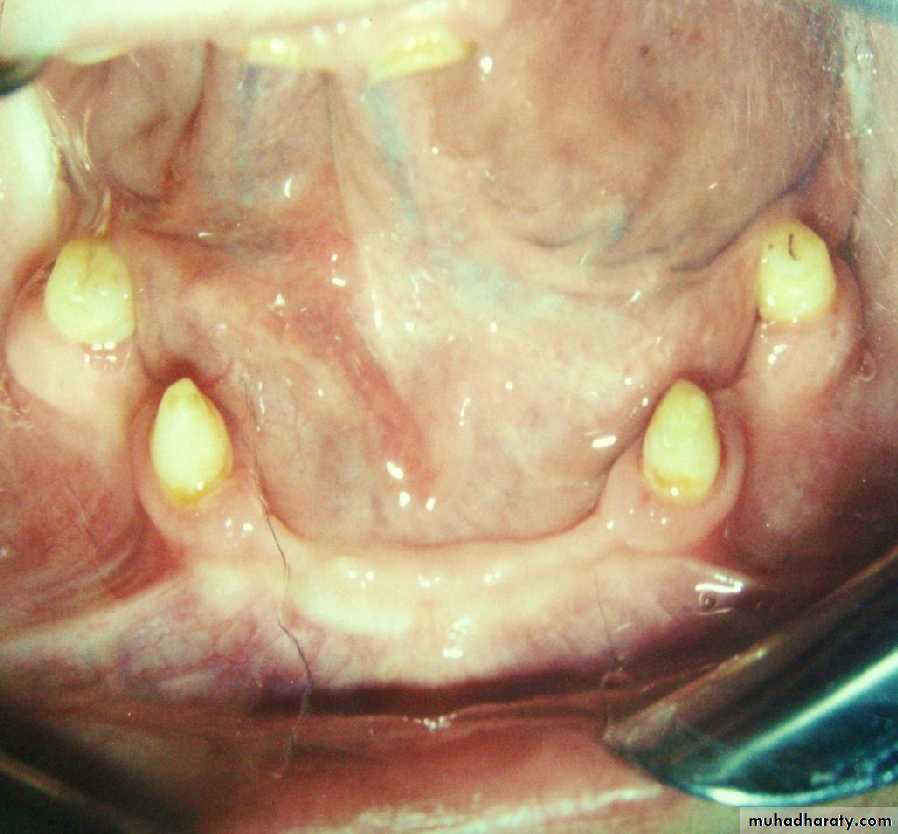

• and the opposing.• 1) Long (6-8mm):

•

• heavily tapered facially.

• less tapered lingually.

• gingival 1/3 approximately parallel.

• a heavy shoulder at the gingival margin , if a secondary metal coping will be placed.

• teeth are usually vital.

• 2) Medium (4-6mm):

• a) usually conical with greater taper on all surfaces.• b)usually used with a bar.

• c) tooth may or may not be vital.